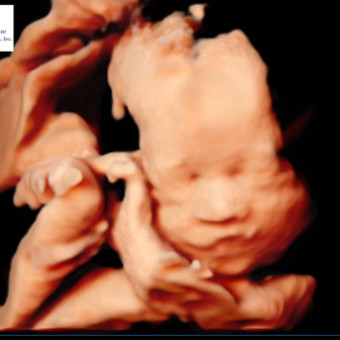

We are so excited to meet baby Claira Selby Baker 💕 Thank you for any contributions to help us prepare for her arrival 💗💗